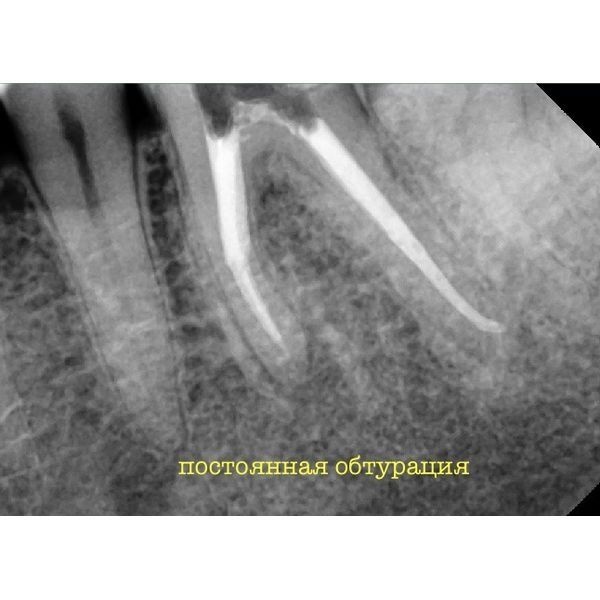

Уже после первой процедуры все симптомы прошли. Следующее посещение назначили через 2 недели, 16 ноября. Пациенту извлекли второй фрагмент и запломбировали каналы с использованием гуттаперчи.